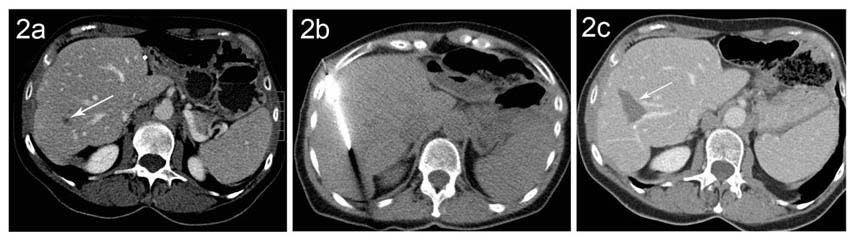

Abbildung (1a) CT eines kleinen HCC (Pfeil) bei einem Patienten mit Leberzirrhose (1b) In der Verlaufskontrolle 6 Monate nach Radiofrequenzablation zeigt sich ein nekrotisches Areal (Pfeil) ohne Hinweis auf Resttumor im Bereich des ehemaligen HCC. (1c) 4 Jahre später ist das Nekroseareal (Pfeil) deutlich kleiner. Ein Rezidiv-Tumor ist weiterhin nicht vorhanden.

Abbildung (2a) CT einer Patientin mit einer einzelnen kleinen kolorektalen Rezidiv-Lebermetastase im rechten Leberlappen (Pfeil). (2b) CT-gezielte Platzierung der Radiofrequenznadel mit der Spitze im Bereich der Metastase (2c) In der Verlaufskontrolle zeigt sich der Behandlungserfolg mit einem Nekroseareal (Pfeil) im Bereich der Metastase ohne Hinweis auf einen Resttumor.